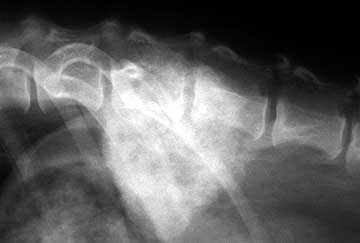

The arrow on the radiograph below points to vertebral changes that occur secondary to nerve dysfunction. It is something we seen in dogs with spinal arthritis called spondylosis along with a problem with the disks called IVD (Intervertebral Disk Disease).

In this radiograph the body is trying to stabilize a subluxated vertebrae by laying down extra bone. Unfortunately, these changes on the radiograph become apparent many months to years after the initial incident that caused the nerve dysfunction. With VNA we now have a diagnostic and treatment capability to prevent these severe boney changes from establishing themselves.

This problem at L3-4 is in mid-back